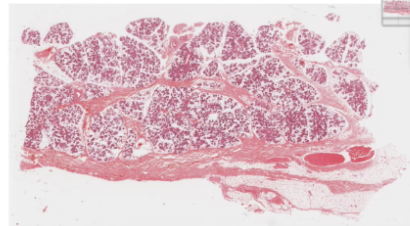

Parotid Salivary gland:

ALL Serous

Round basaly located nuclei

Striated duct visible below

Duct with stirations, representing basal infoldings